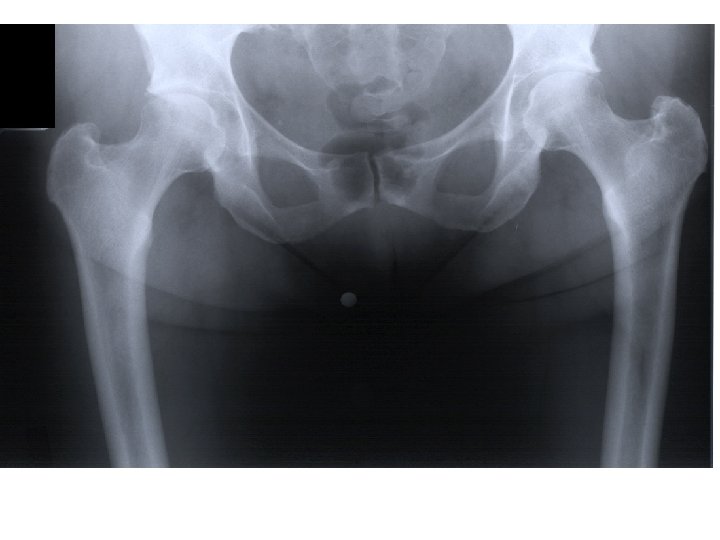

Alt taraf (extremite) kemikleri Cingulum pelvicum Os coxae (2) Pars libera membri inferioris Os femoris (2) Os patellae (2) Os tibiae (2) Os fibulae (2) Ossa tarsi Os tali (2) Os calcanei (2) Os naviculare (2) Os cuboideum (2) Os cuneiforme mediale (2) Os cuneiforme intermediale (2) Os cuneiforme laterale (2) Ossa metatarsi (10) Phalanges (28) Toplam: 62